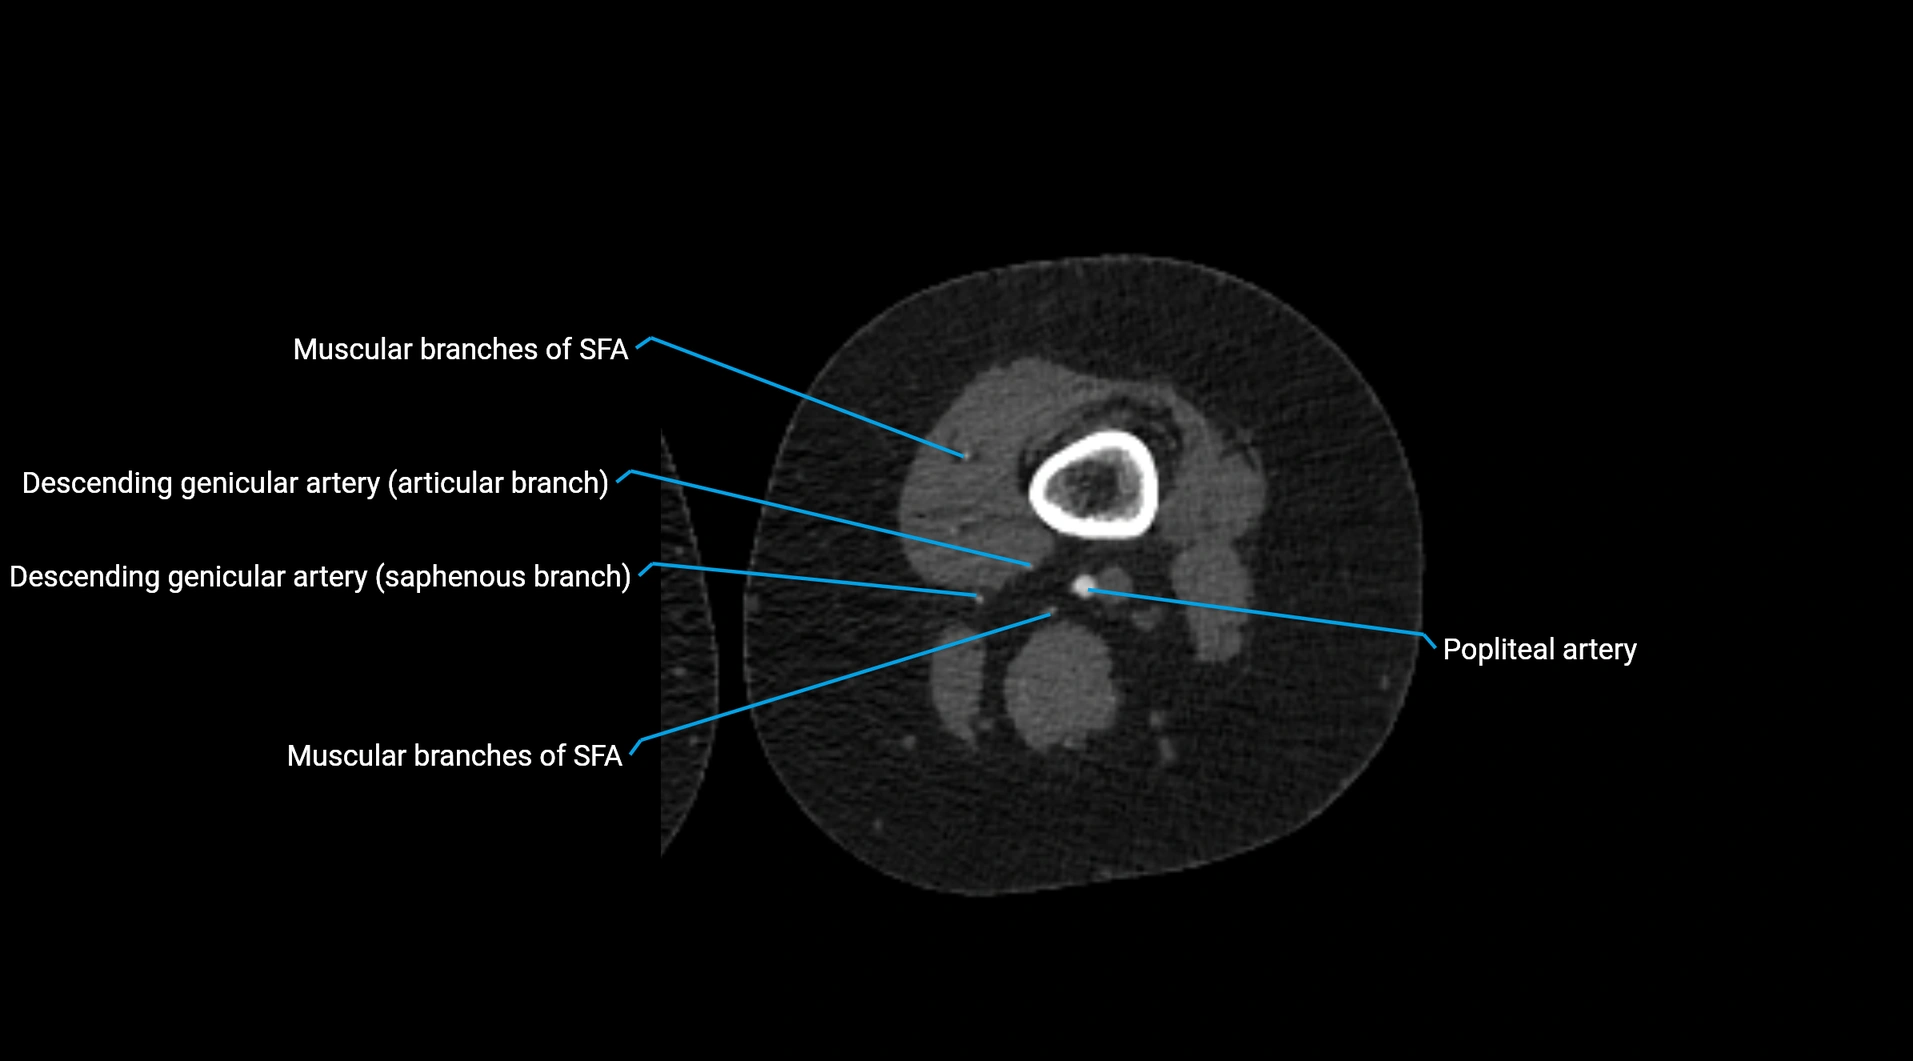

Contrast-enhanced CT (CTA):

• Gold standard for abdominal aortic imaging

• Provides excellent detail of lumen, wall, aneurysm, thrombus, and branch vessels

• Multiplanar and 3D reconstructions help in aneurysm measurement, stent graft planning, and dissection evaluation

• Detects acute rupture, traumatic injury, or occlusion with high sensitivity